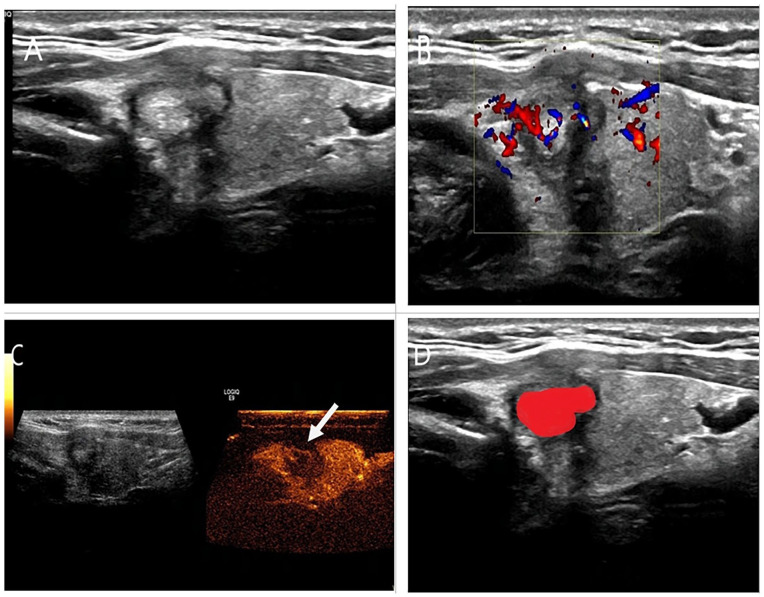

This study aims to establish and validate an ultrasound radiomics nomogram for preoperative prediction of central lymph node metastasis in papillary thyroid microcarcinoma (PTMC) before operation. A retrospective analysis conducted on ultrasonic images and clinical features derived from 288 PTMC patients, who were divided into training cohorts (n = 201) and validating cohorts (n = 87) in a ratio of 7:3 base on the principle of random allocation. Radiomics features were extracted from the PTMC patients after ultrasonic examination, followed by dimension reduction and characteristic selection to construct the radiomics score (Radscore) using LASSO regression analysis. Subsequently, the models, ultrasound features plus clinical features (US-Clin), radiomics score model, and combined model of clinical features plus ultrasound features and Radscore (Combined-model) were built through multi-factor logistic regression analysis. After that, the nomograms were developed for visualization and presentation of these models. The discriminative power, calibration and clinical utility of the nomogram models were evaluated in the training and validating cohorts. The Radscore model comprised 12 carefully selected features. The independent risk factors for conventional ultrasound features and clinical features of PTMC in predicting CLNM included age <45 years, tumor envelope invasion, male gender and presence of microcalcifications, while the enhanced ultrasound features risk factor was extrathyroidal expansion. The combined model showed good performance in predicting PTMC CLNM, with AUCs of 0.921 and 0.889 in the training and validating cohorts, respectively. And DCA based on the prediction model showed good clinical utility. The nomogram developed based on preoperative clinical data, ultrasound features, and Radscore of PTMC patients can more accurately predict central lymph node metastasis (CLNM) in PTMC patients. However, it needs to be validated for clinical applicability in multicenter studies with larger sample sizes and combined with genomic mutation analyses of the tumors.